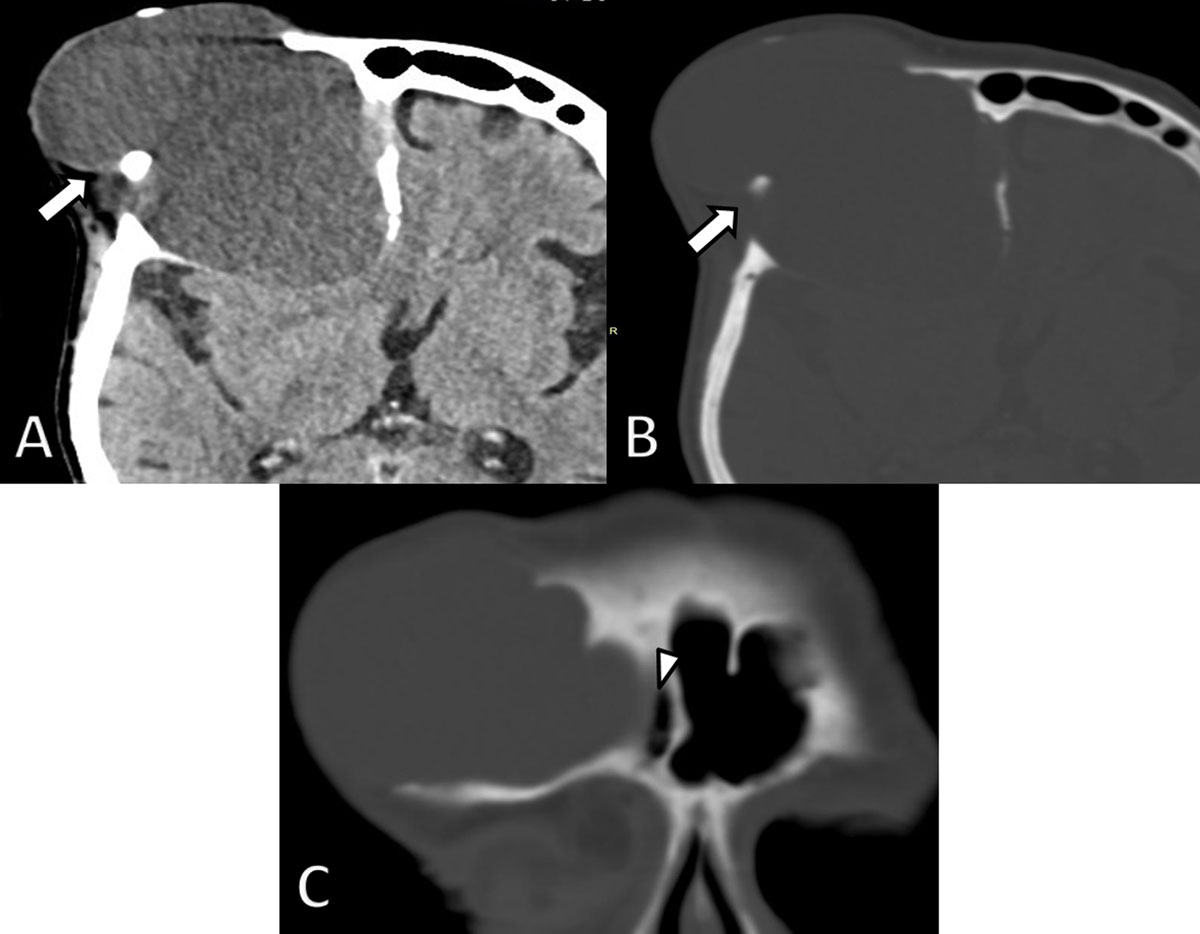

Subsequent MRI of the brain (Figure 2) depicted a well-defined expansile mass being slightly hyperintense on T1-weighted images (WI) and markedly hyperintense on T2-WI. A neurosurgical consult was planned but the patient did not show up. The patient was readmitted four years later because of recurrent falls and memory loss. Repeated CT (Figure 3) and MRI (Figure 4) demonstrated progressive expansion of the mass with increased destruction of the frontal bone. Based on the location at the frontal sinus and the imaging features, a presumptive diagnosis of a giant frontal mucocele was made, which was confirmed upon neurosurgical resection.

Figure 3

Axial non-enhanced CT images four years later. A. Soft tissue and B. bone window demonstrate considerable growth of the lesion (arrows) and a decrease in density. There is increased osteolytic destruction of the frontal bone and progressive extra-axial extension into the brain with mass effect on the frontal horn of the lateral ventricle. C. Coronal reformatted CT image shows an intimate relationship of the lesion with the right frontal sinus (arrowhead).